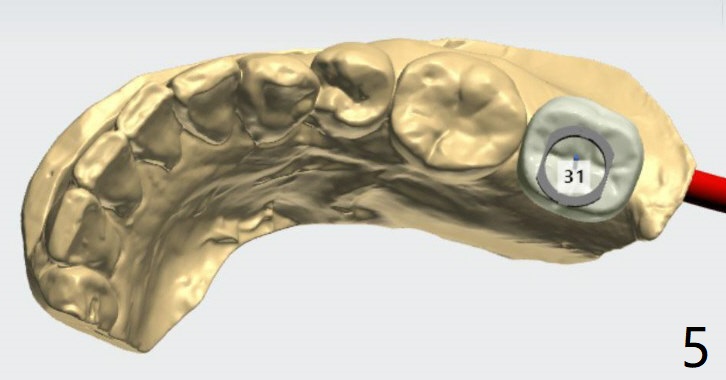

Seven months post socket preservation. Due to coronavirus, the surgery is postponed for 3 months. When the patient returns, take a PA for density check using sensor I. Also take a PA for #3 implant. Take 5x5 pre- (crestal cortex formation? (10 months post socket preservation)) and post-op.